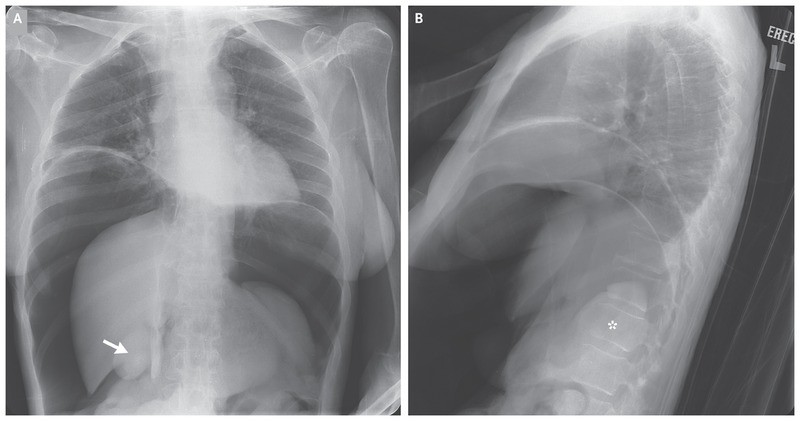

Plain-film radiographs of the chest obtained with the patient in the frontal and lateral positions revealed evidence of pneumoperitoneum, with gas extending from the infradiaphragmatic region to the inferior margin of the liver, outlining the gallbladder (Panel A, arrow). Gas outlined the spleen on the lateral view (Panel B, asterisk).

The findings were highly suggestive of bowel perforation. The decision was made to pursue comfort care, in accordance with the patient’s stated goals. A bedside venting procedure was performed to decompress the abdomen and provide symptomatic relief. The patient died shortly thereafter.